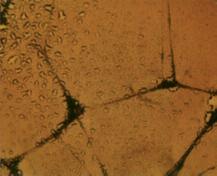

La foto nella pagina a fianco mostra una sezione trasversale al microscopio del fegato di un paziente con ‘leucemia linfatica’. Ciascuno dei piccoli puntini viola nella foto è un globulo bianco (in questo caso linfocita) che ha invaso il tessuto del fegato (aree rosa).

Considerando l’enorme quantità di questi puntini viola e il numero di enzimi che assimilano il collagene che ciascuno produce, è facile prevedere l’ingente distruzione del tessuto connettivo e il danno apportato all’organo da questo tipo di cancro.

Immagine al microscopio della leucemia linfatica

Globuli bianchi affetti di cancro (linfociti) invadono il fegato L’enorme quantità di collagenasi prodotte da queste cellule distruggono l’organo e causano insufficienza epatica.